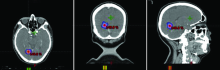

| [2] | 赵永瑞, 高莹, 陈怡东, 徐建堃. 基于直线加速器的分次立体定向放疗对小体积脑转移瘤的有效性及安全性[J]. 国际肿瘤学杂志, 2023, 50(3): 138-143. |